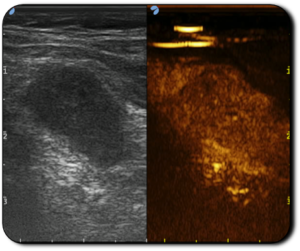

Il controllo ecografico a due anni dal trattamento ha evidenziato la riduzione del volume del nodulo del 70% rispetto al volume basale.

Immagini ecografiche pre trattamento e a due anni di follow-up in cui si evidenzia la riduzione del nodulo

Immagini per gentile concessione del Dott.ssa Rago (Ospedale Cisanello, Pisa)